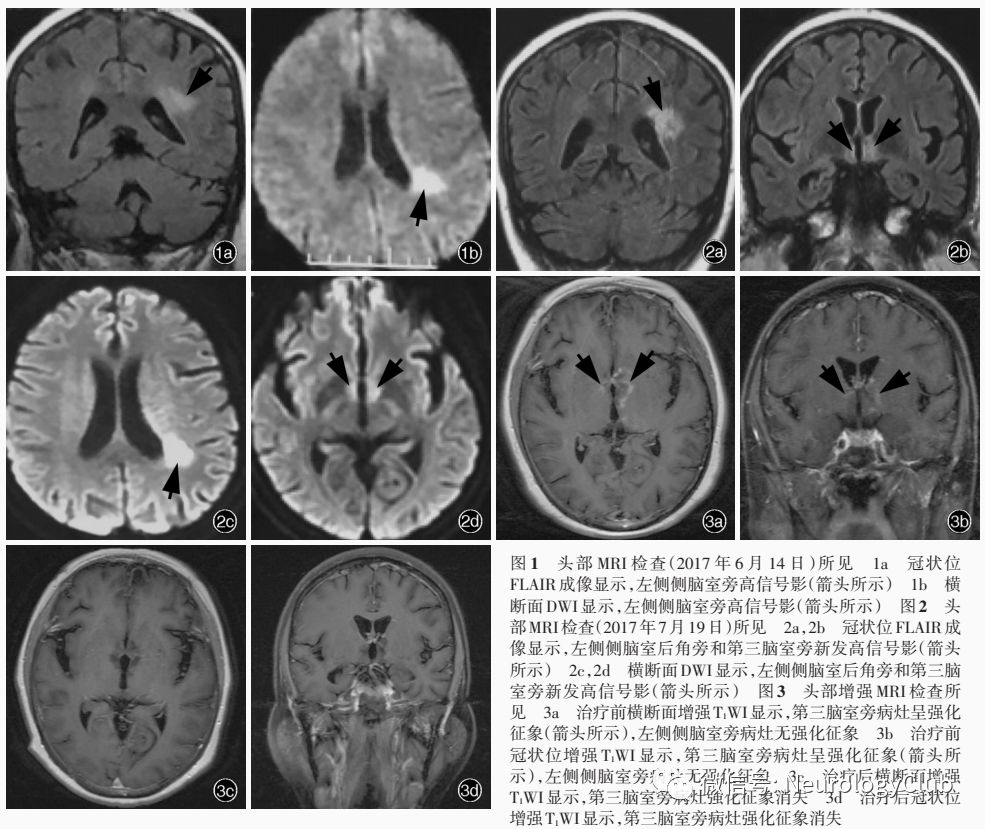

患者女性,62岁,因头晕、恶心、睡眠增多2月余伴精神行为异常1个月,于2017年8月10日入院。患者2月余前(2017年5月25日)乘坐汽车途中出现头晕,恶心,呕吐胃内容物2次,自觉双下肢无力,持续不缓解,但自主行走不受影响;此后逐渐出现精神较差,睡眠增多,自发言语减少。当地医院行头部CT检查未见明显异常,临床诊断为“脑供血不足”,予氯吡格雷静脉滴注(具体剂量不详),症状无明显改善。遂转诊至上级医院,实验室检查(6月12日)血清钠131.90mmol/L(135-145mmol/L);头部MRI检查(6月14日)显示,左侧侧脑室后角旁新发梗死灶,双侧额叶软化灶,周围神经胶质增生(图1);MRA显示,左侧大脑后动脉轻度局限性狭窄,临床考虑“缺血性卒中”,予补钠和改善循环治疗(具体方案不详),头晕和恶心症状好转,但睡眠进一步增多,唤醒后对答切题,出现自言自语,似梦呓,间断性出现右肩抖动、右手摸索动作和反复咂嘴动作,行走时右下肢拖曳。此后嗜睡症状进一步加重,当地医院复查血清钠为122mmol/L(7月12日),予以补钠治疗后恢复至正常水平,但临床症状无明显改善。此后出现低热,体温最高37.3℃,无咽部疼痛、咳嗽、咳痰、流涕,无尿频、尿急、腹泻,当地医院复查MRI(7月19日)显示,左侧侧脑室后角旁、第三脑室周围异常信号影(图2),间断发热,体温最高39.5℃,但无汗,伴咳嗽,胸部CT可见双下肺斑片状渗出影,予头孢曲松钠治疗(具体剂量不详)效果欠佳,高热时予物理降温后体温恢复正常,嗜睡症状进一步加重,唤醒后不识家人,自发言语明显减少且对答不切题。遂于8月2日至我院急诊就诊。体格检查:嗜睡,呼之可睁眼,对答不切题,双侧瞳孔等大、等圆,直径3mm,对光反射灵敏,余脑神经检查未见异常;四肢肌力>3级、肌张力正常,腱反射可引出,双侧病理征阴性,颈项稍强直,颏胸距2横指。8月4日出现发热1次,体温最高38.4℃,物理降温后体温恢复正常。实验室检查:血清免疫学指标抗水通道蛋白4(AQP4)抗体阳性(1∶32);自身抗体谱抗干燥综合征A型抗体(SSA)、抗Ro52抗体弱阳性(Western blotting法),抗甲状腺过氧化物酶(TPO)抗体49.04IU/ml(<34IU/ml)、抗甲状腺球蛋白(TG)抗体122.10IU/ml(<115IU/ml)。腰椎穿刺脑脊液检查(8月7日)外观清亮、透明,压力正常,白细胞计数为8×106/L[(0-5)×10^6/L]、单核细胞计数8×106/L[(0-5)×10^6/L],蛋白定量690mg/L(250-450mg/L),葡萄糖和氯化物正常;细胞学白细胞计数800/0.50ml,激活淋巴细胞阳性;髓鞘碱性蛋白(MBP)1.03nmol/L(≤0.55nmol/L),特异性寡克隆区带(SOB)阳性,抗N-甲基-D-天冬氨酸受体(NMDAR)抗体阳性(1∶100),抗AQP4抗体可疑阳性,副肿瘤相关抗体抗Hu、Yo、Ri抗体阴性,细菌、病毒抗体和真菌培养阴性。头部MRI增强扫描显示,下丘脑和双侧丘脑病灶强化(图3a,3b)。急诊考虑抗N-甲基-D-天冬氨酸(NMDA)受体脑炎,予静脉注射免疫球蛋白(IVIg)0.40g/(kg·d),次日收入院。患者自发病以来,睡眠增多,食欲可,食量增加,若不制止可一直进食,可自主排尿、排便,深睡时偶有大小便失禁,体重无明显下降,无眼干、口干、光过敏、雷诺现象、关节疼痛、口腔和外阴溃疡等免疫性疾病相关表现。

诊断与治疗经过  患者入院后完善各项相关检查。实验室检查:血清钠130mmol/L、血清钾3.10mmol/L(3.50-5.50mmol/L),空腹血糖17.50mmol/L(3.90-6.10mmol/L)、糖化血红蛋白(HbA1c)为8.60%(4.50%-6.30%)、尿糖≥55mmol/L,余血常规、尿常规、便常规+便潜血、肝肾功能试验、甲状腺功能试验、血清电解质、凝血功能、感染4项[乙型肝炎病毒表面抗原(HbsAg)、丙型肝炎病毒(HCV)抗体、梅毒螺旋体(TP)抗体、人类免疫缺陷病毒(HIV)抗体]均于正常值范围。免疫学指标超敏C-反应蛋白(hs-CRP)5.38mg/L(0-3mg/L),红细胞沉降率(ESR)61mm/h(0-20mm/h),抗可提取性核抗原(ENA)抗体阴性。血清肿瘤标志物筛查呈阴性。影像学检查:子宫和双侧附件超声以及胸腹盆腔CT检查未见明显异常;颈椎和胸椎MRI增强扫描未见髓内异常信号影。神经电生理学检查:脑电图显示,前部导联较多散在低至中波幅4-7Hz慢波,以及少量散在不规则低至中波幅2-3Hz慢波。临床诊断抗NMDA受体脑炎合并视神经脊髓炎谱系疾病。继续静脉注射免疫球蛋白0.40g/(kg·d),连续5d后症状无明显改善,并出现尿潴留,遂导尿,尿量较多(约4000ml/d),尿常规尿比重<1.005(1.005-1.030),遂静脉滴注甲泼尼龙1000mg/d(×5d)冲击治疗并序贯口服泼尼松60mg/d(每2周减量5mg至停药),以及吗替麦考酚酯1.50g/d口服,同时予钙剂、胃黏膜保护剂和钾剂等预防激素不良反应以及积极降糖治疗。完善下丘脑-垂体-肾上腺(HPA)轴检查:血浆渗透压、尿渗透压均于正常值范围,血清胰岛素样生长因子(IGF)、生长激素(GH)、促肾上腺皮质激素(ACTH)、总皮质醇、黄体生成素(LH)、卵泡刺激素(FSH)、雌二醇、孕激素、睾酮、泌乳素(PRL)均于正常值范围。入院后次日(8月11日)出现间断性发热,体温最高38.6℃,不排除感染可能,予头孢他啶(1g/次、3次/d)、甲硝唑(0.50g/次、3次/d)、环丙沙星(0.20g/次、2次/d)静脉滴注抗感染治疗。完善病原学检查:咽拭子甲型和乙型流感病毒、EB病毒(EBV)DNA、TORCH10项[弓形虫(TOX)、风疹病毒(RV)、巨细胞病毒(CMV)、I型和II型单纯疱疹病毒(HSV-1和HSV-2)]均呈阴性,血清和脑脊液流行性乙型脑炎病毒[亦称日本乙型脑炎病毒(JEV)]IgM呈阴性;降钙素原(PCT)于正常值范围;结核菌素纯蛋白衍生物(PPD)呈阳性,血清结核分枝杆菌感染T细胞斑点试验(T-SPOT.TB)呈阴性;发热时3次进行血培养均呈阴性;胸部CT显示,双肺间质纹理增多,双肺下叶多发淡片、索条影,考虑炎症改变可能,双侧肺门和纵隔多发小淋巴结,部分钙化。进行2次尿培养,第1次呈阴性,第2次培养出热带念珠菌、白念珠菌,考虑定殖菌感染。反复查找未发现明确感染证据,结合发热时无汗、物理降温后体温恢复正常特点,考虑中枢热可能性大,遂于8月24日停用抗生素。静脉注射免疫球蛋白、激素和免疫抑制剂联合治疗,日间睡眠逐渐减少,反应能力逐渐改善,尿量逐渐正常。8月22日复查实验室指标:血清抗AQP4抗体阴性;腰椎穿刺脑脊液外观透明、清亮,白细胞计数7×106/L,单核细胞计数6×106/L、多核细胞计数1×106/L,蛋白定量690mg/L,葡萄糖、氯化物和乳酸均于正常值范围;细胞学白细胞计数500/0.50ml,轻度淋巴细胞反应;细菌、病毒、真菌和结核分枝杆菌培养呈阴性;特异性寡克隆区带呈弱阳性,IgG合成率10.34mg/24h;髓鞘碱性蛋白1.37nmol/L;抗NMDAR抗体阳性,抗AQP4抗体阴性。复查头部MRI,第三脑室旁病灶强化征象消失(图3c,3d)。脑电图显示,各导联多发4-7Hz慢波、散在2-3Hz慢波,左侧颞区可见散在1.50Hz慢波。T细胞亚群检测,CD19+B细胞比例明显增加,遂于8月31日将吗替麦考酚酯增量至2g/d,日间嗜睡明显改善,偶识家人,可自发简单言语。患者住院22d,出院后3个月随访时,嗜睡症状消失,可识家人,简单言语交流,自主进食,自主大小便,独立行走,右下肢拖曳消失。

放射科医师  抗NMDA受体脑炎患者头部MRI通常无特异性,亦可无明显异常,或仅散在皮质和皮质下点片状T2WI和FLAIR成像高信号,部分可见边缘系统病灶,少数兼有中枢神经系统脱髓鞘病变特点,白质或脑干、脊髓受累。该例患者MRI无边缘系统受累表现,病灶主要位于左侧侧脑室旁和第三脑室旁,伴轻度强化,这种主要累及室管膜周围的病灶符合视神经脊髓炎谱系疾病的影像学特点。